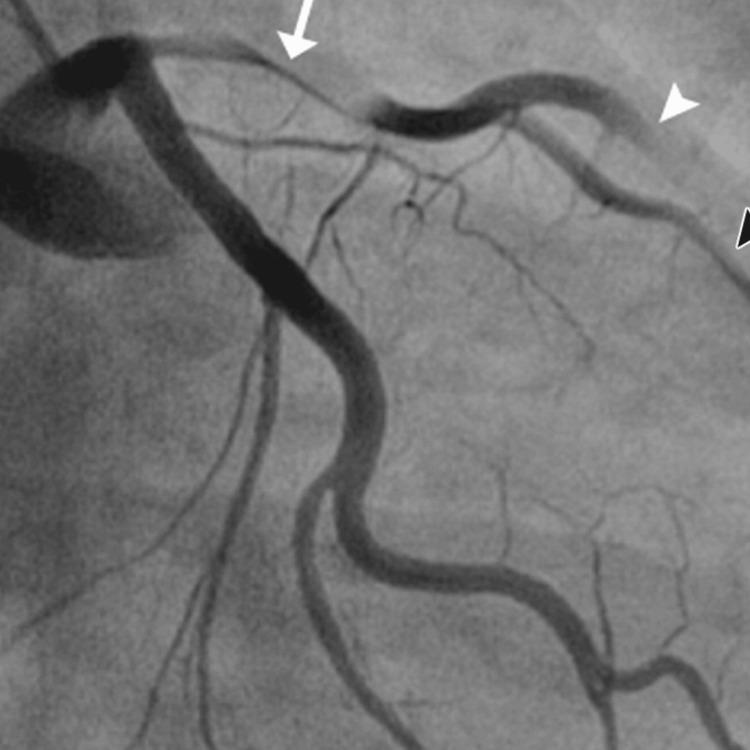

Further diagnostic investigation was pursued through cardiac catheterization, which uncovered a diffuse dissection involving the mid-distal portion of the LAD artery, the posterior descending artery (PDA), the second diagonal branch of the LAD, and the first obtuse marginal branch (OM1) of the left circumflex artery. These findings confirmed the diagnosis of SCAD. The echocardiogram supported these findings showing a left ventricular ejection fraction (LVEF) between 35% and 40% and a fixed mural thrombus on the apical wall of the left ventricle, which are indicators of significant cardiac dysfunction.

The patient’s urine toxicology screen returned positive for Δ9-THC, indicating recent marijuana use, which could have contributed to his cardiovascular event given the known hemodynamic effects of cannabinoids. The angiographic findings illustrating the progression and extent of the coronary artery dissections are sequentially shown in Figures 1–3, providing visual confirmation of the clinical and diagnostic narrative described above.